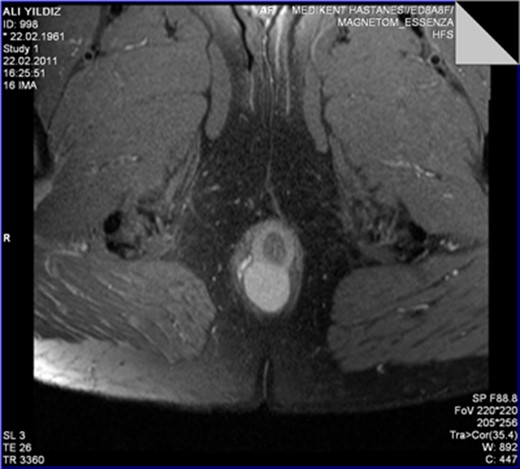

The MRI scan revealed a well-circumscribed homogeneous mass ovoid in shape, measuring 3.4 × 3.5 × 2.7 cm3 in diameter located in the intersphincteric plane, originating from the posterior aspect of the internal anal sphincter just in the midline, growing away from the lumen, displacing and stretching the external anal sphincter (Figs 1 and 2).

The leiomyoma originating from the internal anal sphincter growing far from the lumen stretching and pushing away the external anal sphincter.

The perinal fistula passing intersphincterically upwards in close relation to the leiomyoma without invasion.

T2A weighed MR sequences showed moderate to low signal intensity, and in post-contrast series there was no internal contrast uptake, necrosis, lymphadenopathy or cystic component. The perianal fistula was intersphincter, fistula tractus passing cranially and very close to the right lateral border of the mass without showing any sign of invasion. During surgery internal orifice of the fistula was identified at the level of dentate line. A stylet was passed through the fistula tractus which was confirmed to be intersphincteric and to be directed cranially in close relation to the right lateral border of the lesion without any signs of invasion. Fistulotomy is performed, dissection was performed meticulously without interruption of the pseudocapsule of the mass, and commenced up to the level where the mass was originating from internal anal sphincter. A few muscle fibers were carefully included into the specimen in order to preserve the integrity of the pseudocapsule and leave the anal sphincter intact. Histopathological examination showed fascicles of uniform spindle cells, with abundant eosinophilic cytoplasm, lack of nuclear atypia, lack of necrosis and practically inexistent mitotic activity (<1 mitoses/50 high power fields). The immunohistochemistry analysis showed a strong positivity for desmin and alpha smooth muscle actin and was negative for S100, CD117 and CD34 stains. This pattern is compatible with the diagnosis of leiomyoma. Postoperative course was uneventful. No complaints of anal incontinence were described by the patient. Patient is now symptom free for 8 years of follow-up.